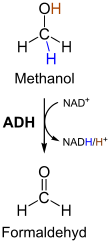

Unverstoffwechseltes Methanol ist nur von geringer Giftigkeit (Toxizität). Giftig sind seine Abbauprodukte (Metaboliten), so der durch ADH (Alkoholdehydrogenase) gebildete Formaldehyd (vgl. Abbildung rechts) und die daraus entstehende Ameisensäure. Insbesondere Letztere führt nach einer häufig ohne Symptome verlaufenden Latenzzeit von 6 bis 30 Stunden zur Ausbildung einer metabolischen Azidose. Ameisensäure wird vom menschlichen Stoffwechsel nur sehr langsam abgebaut und sammelt sich so während des vergleichsweise zügigen Abbaus des Methanols im Körper an. Die Giftigkeit des Formaldehyds ist bei der Methanolvergiftung umstritten. Es wird durch die katalytische Einwirkung des Enzyms Aldehyddehydrogenase sehr schnell weiter zur Ameisensäure abgebaut, so dass es zu keiner Anreicherung von Formaldehyd im Körper kommt. Dosen ab 0,1 g Methanol pro kg Körpergewicht sind gefährlich, über 1 g pro kg Körpergewicht lebensbedrohlich.